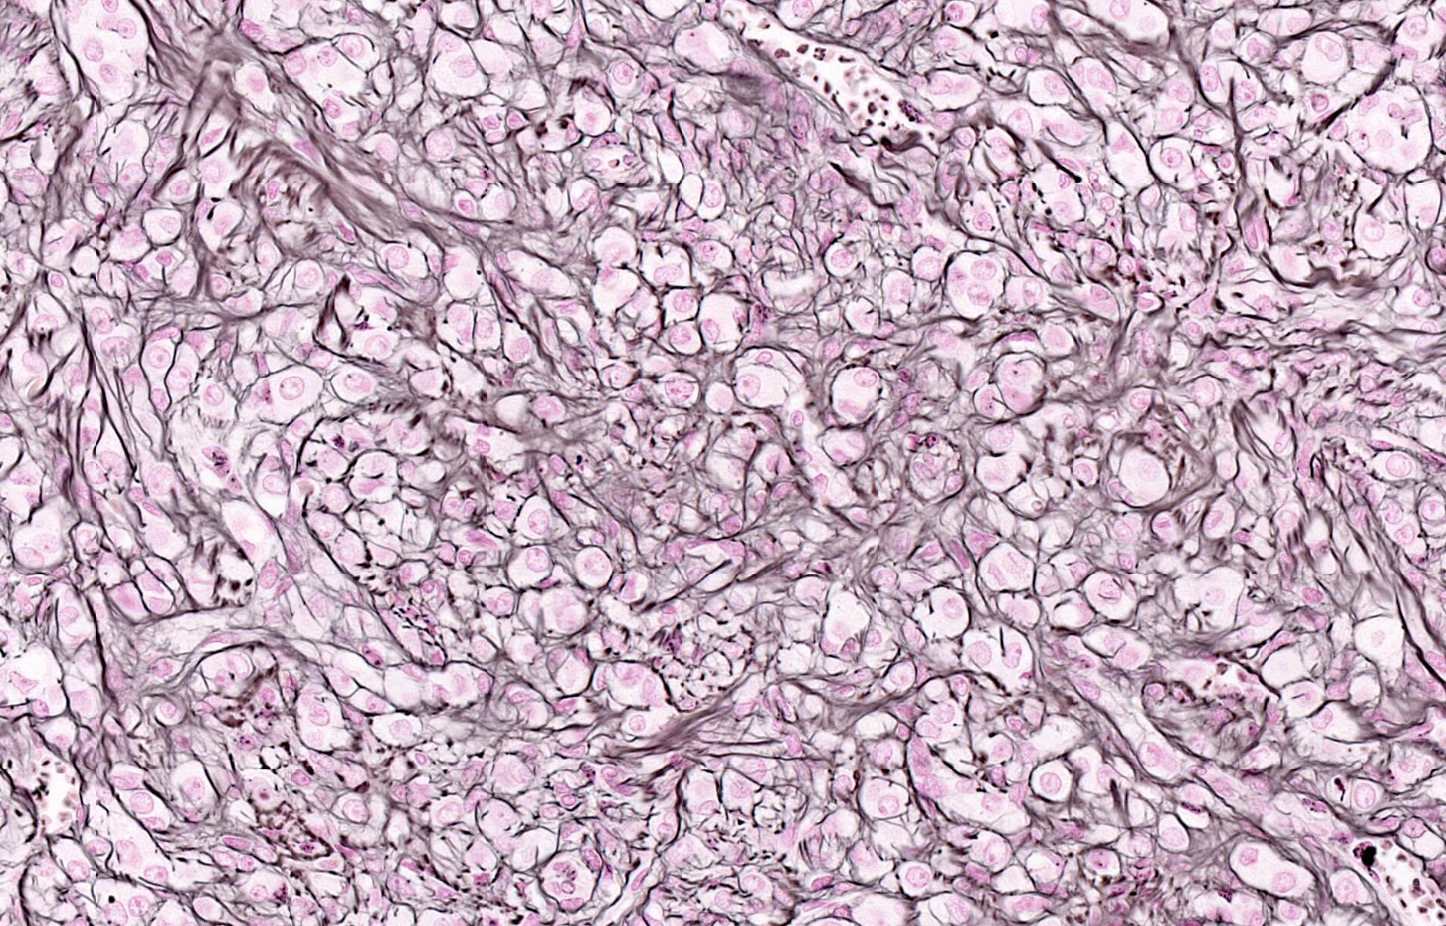

Microscopic (histologic) description

- Predominant population of cells showing ovoid to round nuclei and pale gray cytoplasm, which can be abundant

- Minor component of the tumor may have spindled nuclei, reflecting overlap between fibroma and thecoma

- Indistinct cell membranes impart a syncytial appearance

- Diffuse or nodular growth pattern

- Absent or minimal nuclear atypia

- Mitotic rate usually < 5/10 high power fields

- Hyaline plaques

- Cytoplasmic lipid vacuoles may be present but are not essential

- May show aggregates of cells with brightly eosinophilic cytoplasm (lutein cells)

- Calcification is more common in young patients (Int J Gynecol Pathol 1988;7:343)

- Uncommon features include keloid-like sclerosis, nuclear grooves, bizarre nuclear atypia (Am J Surg Pathol 2014;38:1023)

- Rarely contains a minor component of sex cord elements (Int J Gynecol Pathol 1983;2:227)

- Malignant thecoma: very rare, diagnosis requires diffuse moderate to severe nuclear atypia and high mitotic rate (> 4/10 high power fields) (Am J Surg Pathol 2011;35:e15)

Microscopic (histologic) images

Contributed by Victoria Collins, M.D., Tamara Kalir, M.D., Ph.D., AFIP and @SeoparjooAzmel on Twitter